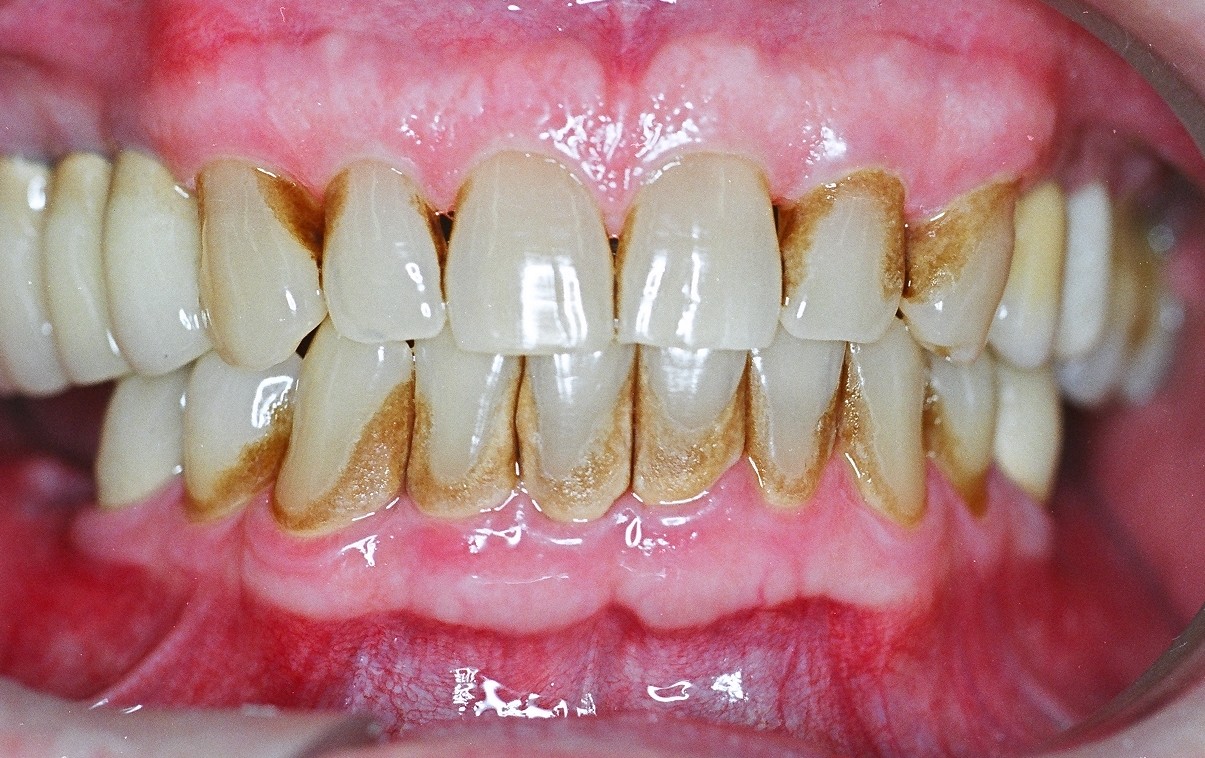

A periodontite agressiva juvenil é uma doença gengival séria que afeta jovens. Ela causa destruição rápida do osso e dos tecidos que sustentam os dentes. O diagnóstico precoce é crucial para evitar a perda dentária.

A periodontite agressiva juvenil, quando não tratada, pode trazer sérias consequências para a saúde bucal. Por isso, a limpeza profissional não é só um cuidado estético, é a base para o controle dessa condição. Dentistas e higienistas têm as ferramentas e o conhecimento para remover aquela placa bacteriana e o tártaro que o dia a dia em casa não alcança. É um passo fundamental para frear a progressão da doença.

Nesse tratamento, o foco é a remoção minuciosa das bactérias. Os profissionais utilizam instrumentos específicos para limpar profundamente as bolsas periodontais, que são aquelas espaços que se formam entre o dente e a gengiva quando a doença avança. O objetivo é criar um ambiente bucal mais saudável, onde a gengiva possa começar a se recuperar e a inflamação diminua. É um trabalho delicado, que exige precisão.